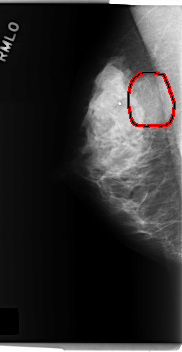

C_0279_1.RIGHT_MLO

RIGHT_MLO LINES 5976 PIXELS_PER_LINE 3088 BITS_PER_PIXEL 12 RESOLUTION 50 OVERLAY

FILE: C_0279_1.RIGHT_MLO.OVERLAY

TOTAL_ABNORMALITIES 1

ABNORMALITY 1

LESION_TYPE MASS SHAPE OVAL MARGINS OBSCURED

ASSESSMENT 4

SUBTLETY 5

PATHOLOGY BENIGN

TOTAL_OUTLINES 1

BOUNDARY